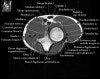

팔꿈치 관절의 MRI 단면 영상

1. Coronal section

1) Collateral ligament

2) Common extensor/flexor tendon group patholgy as well as epicondylitis